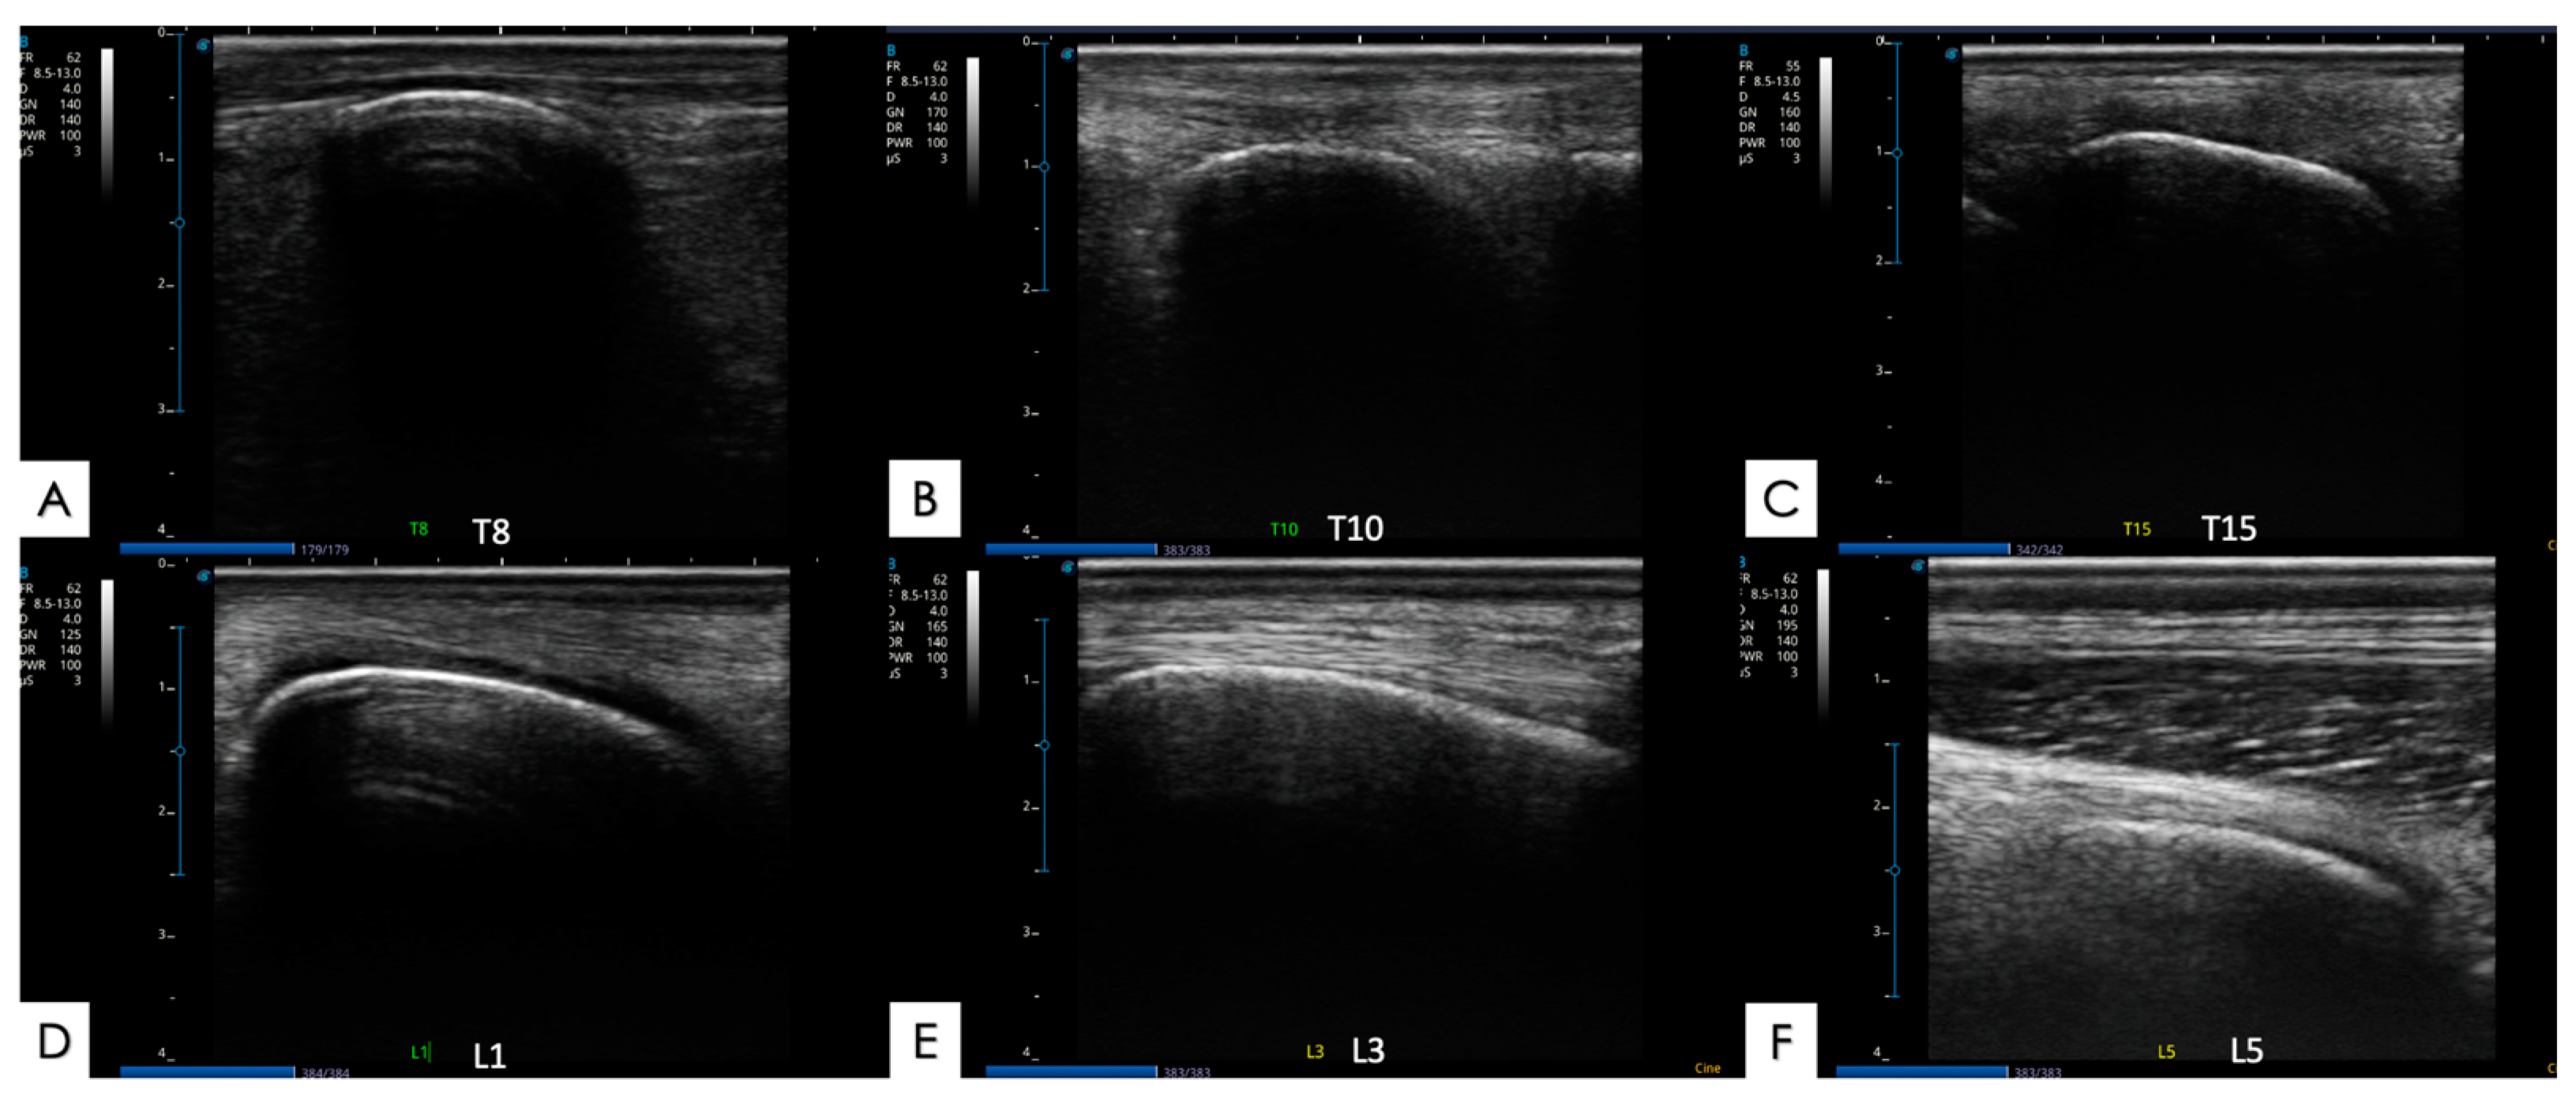

2.5.1. Articular Processes and Epaxial Muscle

2.5.2. Spinous Processes and Supraspinous Ligament